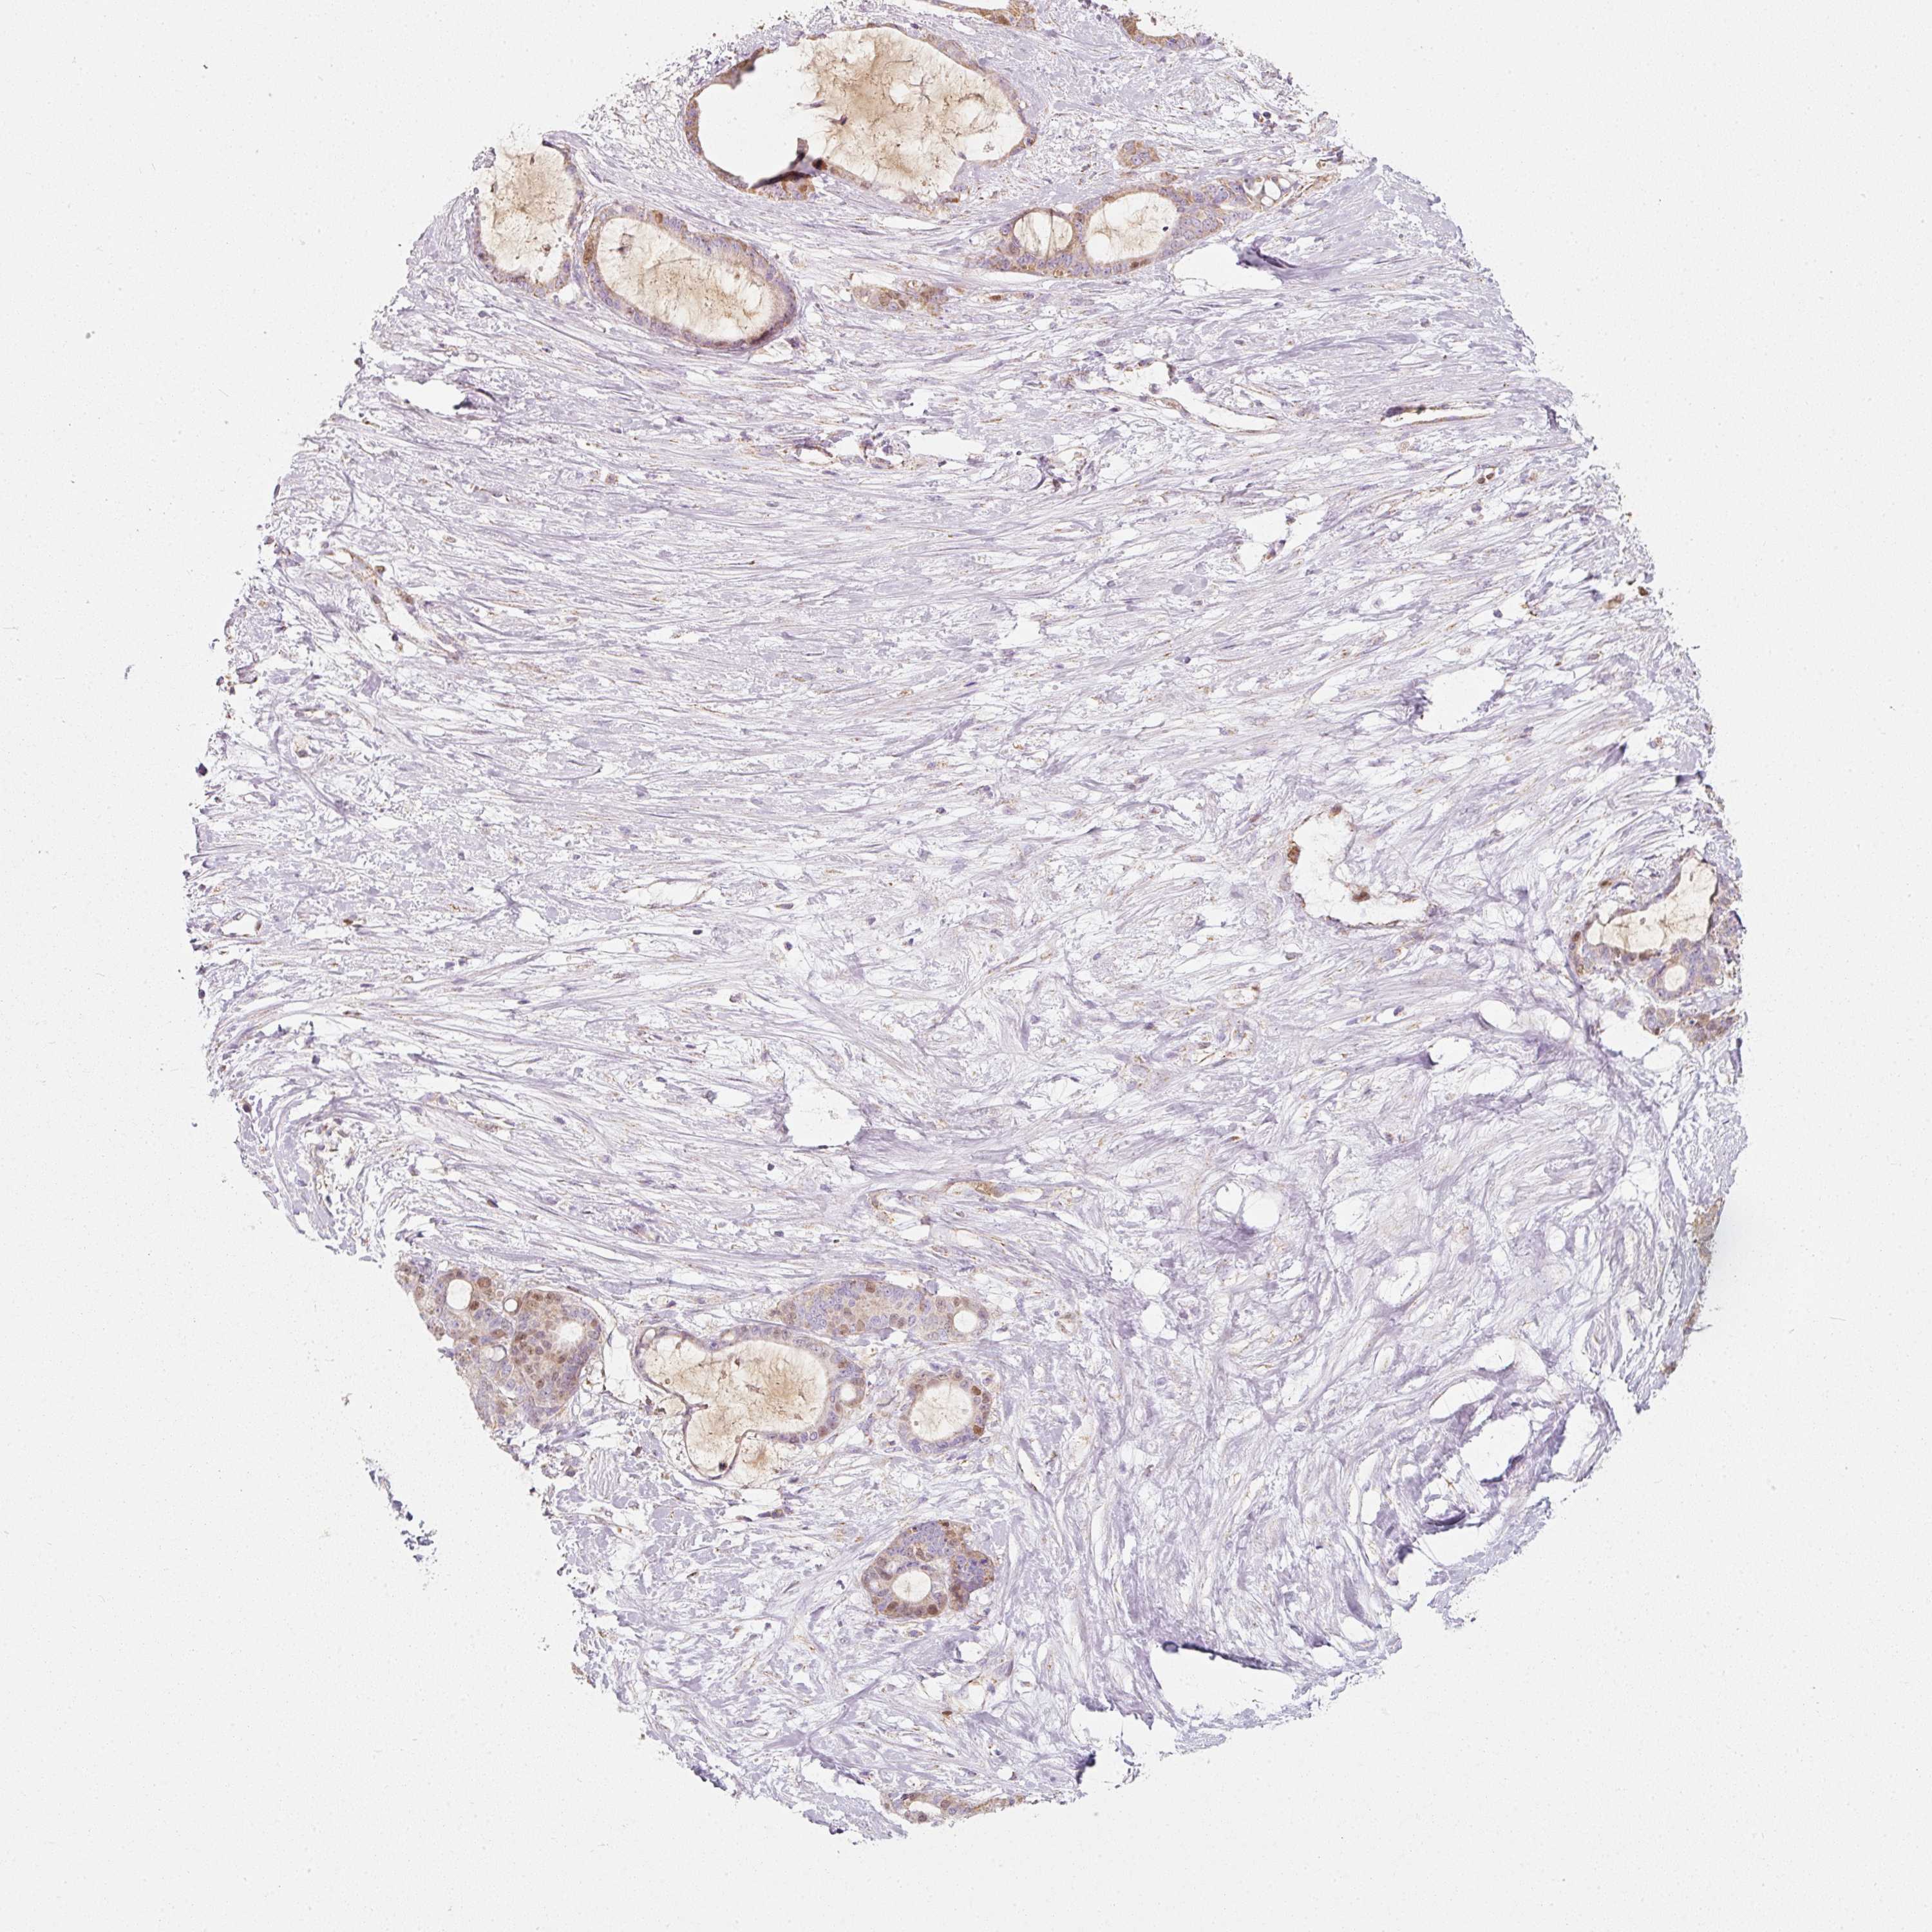

LIVER CANCER - Protein expressioni

A mouse-over function shows sample information and annotation data. Click on an image to view it in a full screen mode. Samples can be filtered based on level of antibody staining by selecting one or several of the following categories: high, medium, low and not detected. The assay and annotation is described here.

Note that samples used for immunohistochemistry by the Human Protein Atlas do not correspond to samples in the TCGA dataset.

Antibody stainingi

Antibody staining in the annotated cell types in the current human tissue is reported as not detected, low, medium, or high, based on conventional immunohistochemistry profiling in selected tissues. This score is based on the combination of the staining intensity and fraction of stained cells.

Each image is clickable and will lead to virtual microscopy that enables deeper exploration of all samples and also displays staining intensity scores, fraction scores and subcellular localization as well as patient and tissue information for each sample.

Antibody HPA054422

Antibody HPA060360

Staining

High

Medium

Low

Not detected

Intensity

Strong

Moderate

Weak

Negative

Quantity

>75%

75%-25%

<25%

None

Location

Nuclear

Cytoplasmic/membranous

Cytoplasmic/membranous,nuclear

Carcinoma, Hepatocellular, NOS

Cholangiocarcinoma